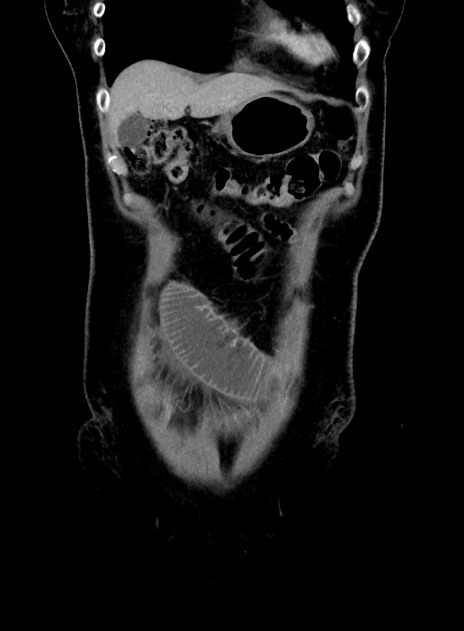

症例9(冠状断像)

【症例】 60歳代女性

【主訴】むかつき、みぞおちの痛み

【現病歴】3日前よりむかつきがあり、食事がとれない。

【既往歴】糖尿病

【身体所見】発熱なし、心窩部圧痛軽度あるも、腹膜刺激症状なし。

【データ】WBC 7400、CRP 1.92

横断像